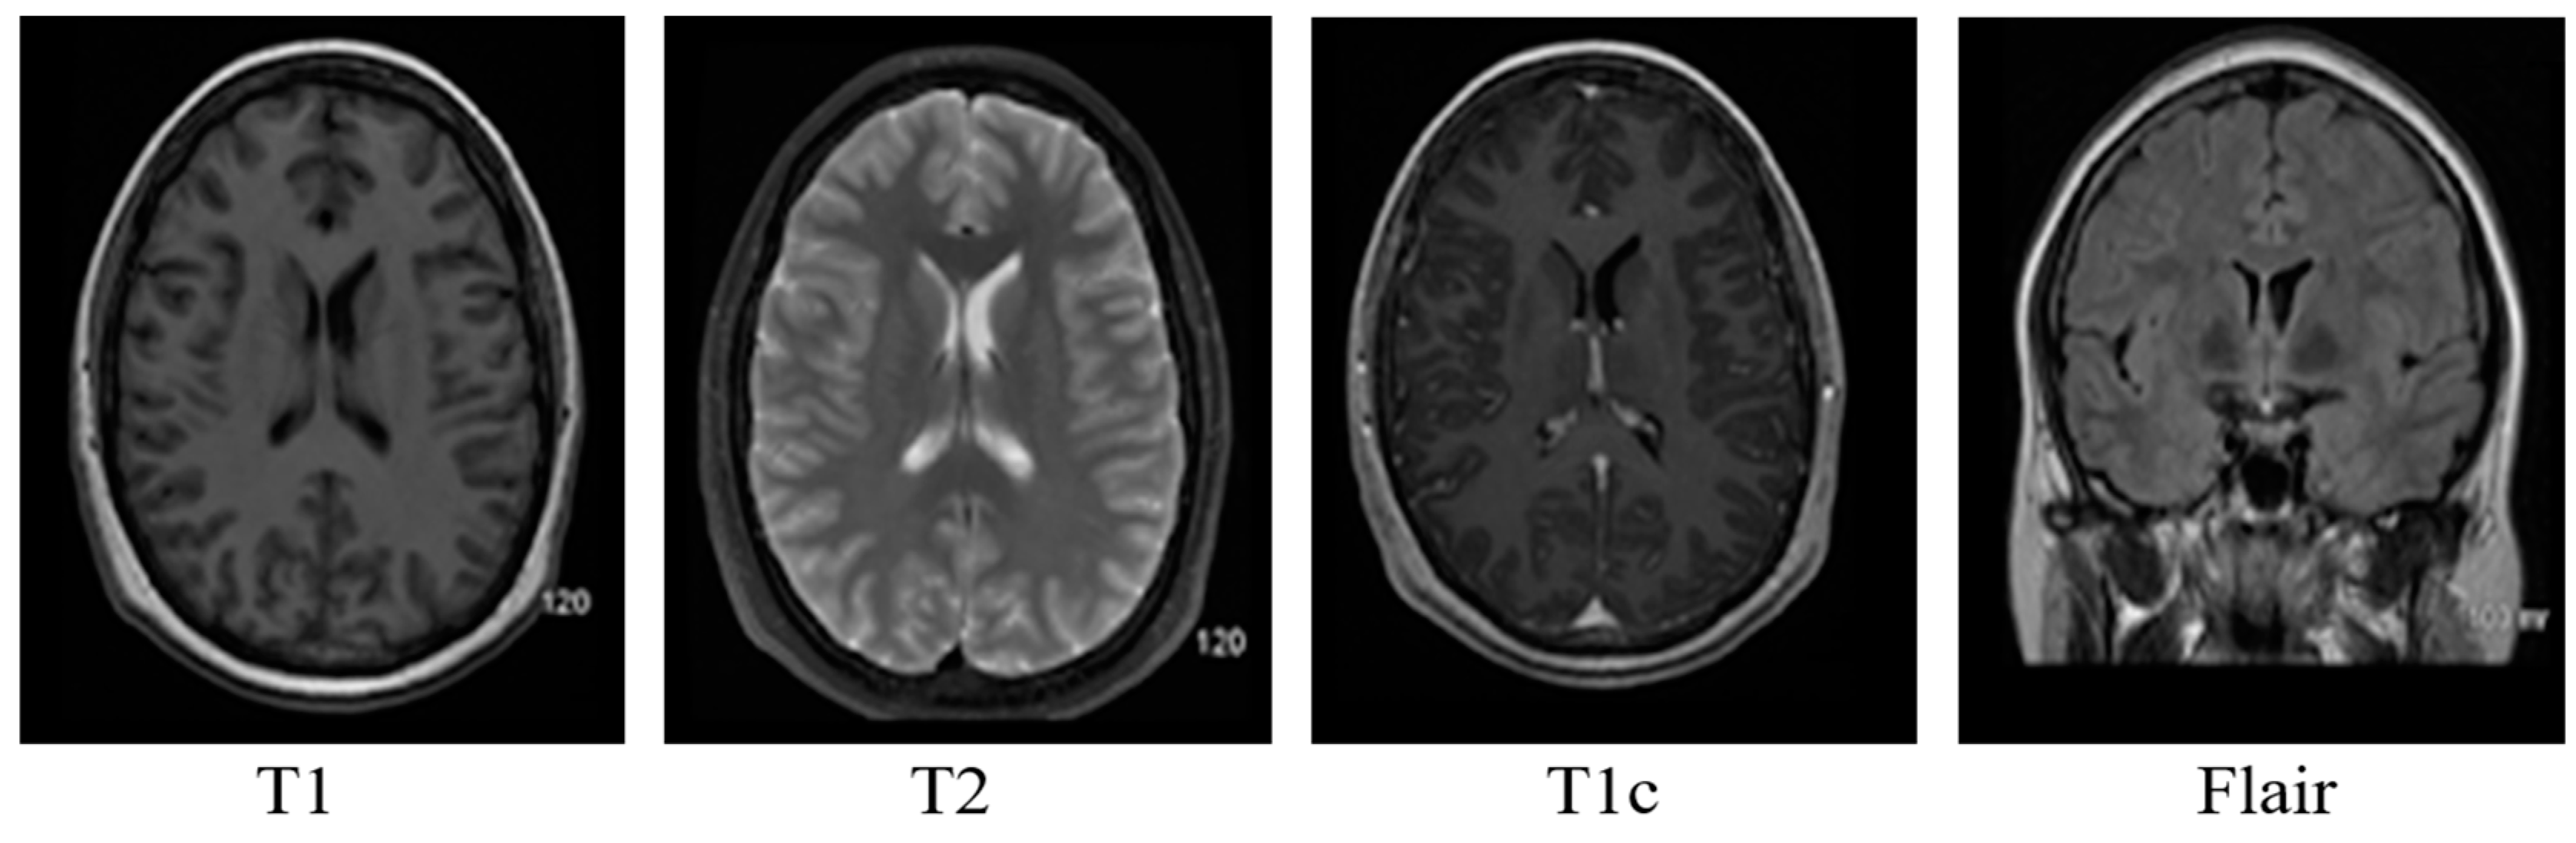

Brain MRI tumors have complicated structures and shapes, which makes the tumor classification and segmentation process more difficult using uni-modality. MRI machines provide an option to capture multimodality images with a more detailed representation of brain tissues [9]. During the MRI scan of a patient, the MRI machine produces different types of MRI sequences including T1, T2, T1c, and Flair, which are based on the Time to Echo (TE), Repetition Time (TR), brightness and contrast values. Figure 3 describes the four different brain MRI modalities and Figure 4 describes the three different types of healthy tissues inside the brain.

Samples of these four modalities (T1, T2, T1c, Flair) are presented in Figure 6. All four modalities have 620 MR images which make a total of 239,320 MR images for all 384 cases and a total of 169,880 MR images 274 train images as shown in Table 2. In BraTS dataset, labels are provided only for the train images so only train images are used for experiments. The dataset is divided into 60% for training, 20% for validation and 20% for the testing. BraTS provides data in MetaImage (.mha) format which is used to store 3D medical images. For each modality of every case, there are 155 slices with 240 × 240 pixel dimensions which are stored in a single mha file.

Figure 6. Sample MR images of T1, T2, T1c and Flair modalities.